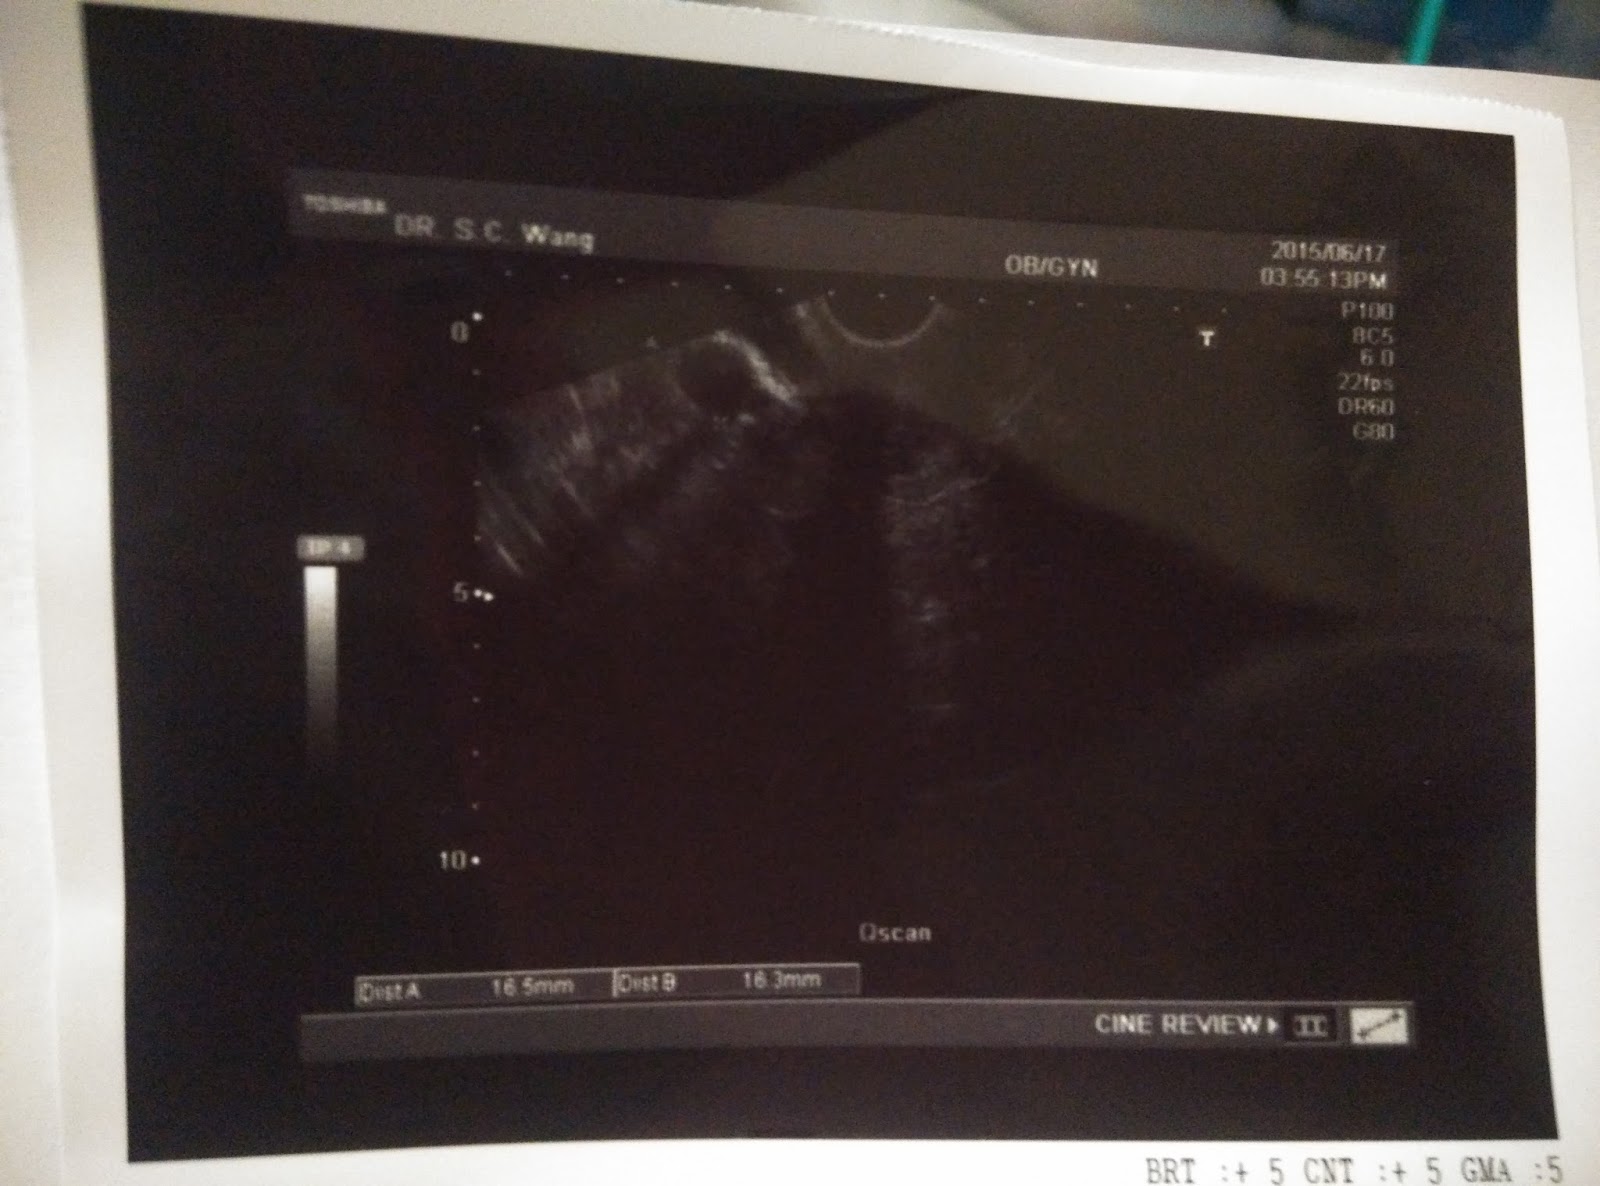

6月17日,星期三。

今天要去黃醫生那裡覆診,看看卵泡及內膜的生長情況。

還好醫生檢查後,卵子還在。

她說已大了一點點,約有1.7cm,

但我問她看照片上只有1.65cm,不是比之前還細了嗎。

她解釋因角度的問題,剛剛看到有其他角度是大一點的。

至於內膜就厚了一點點,由5mm增厚至6mm。

雖然是厚了,但依然未夠。